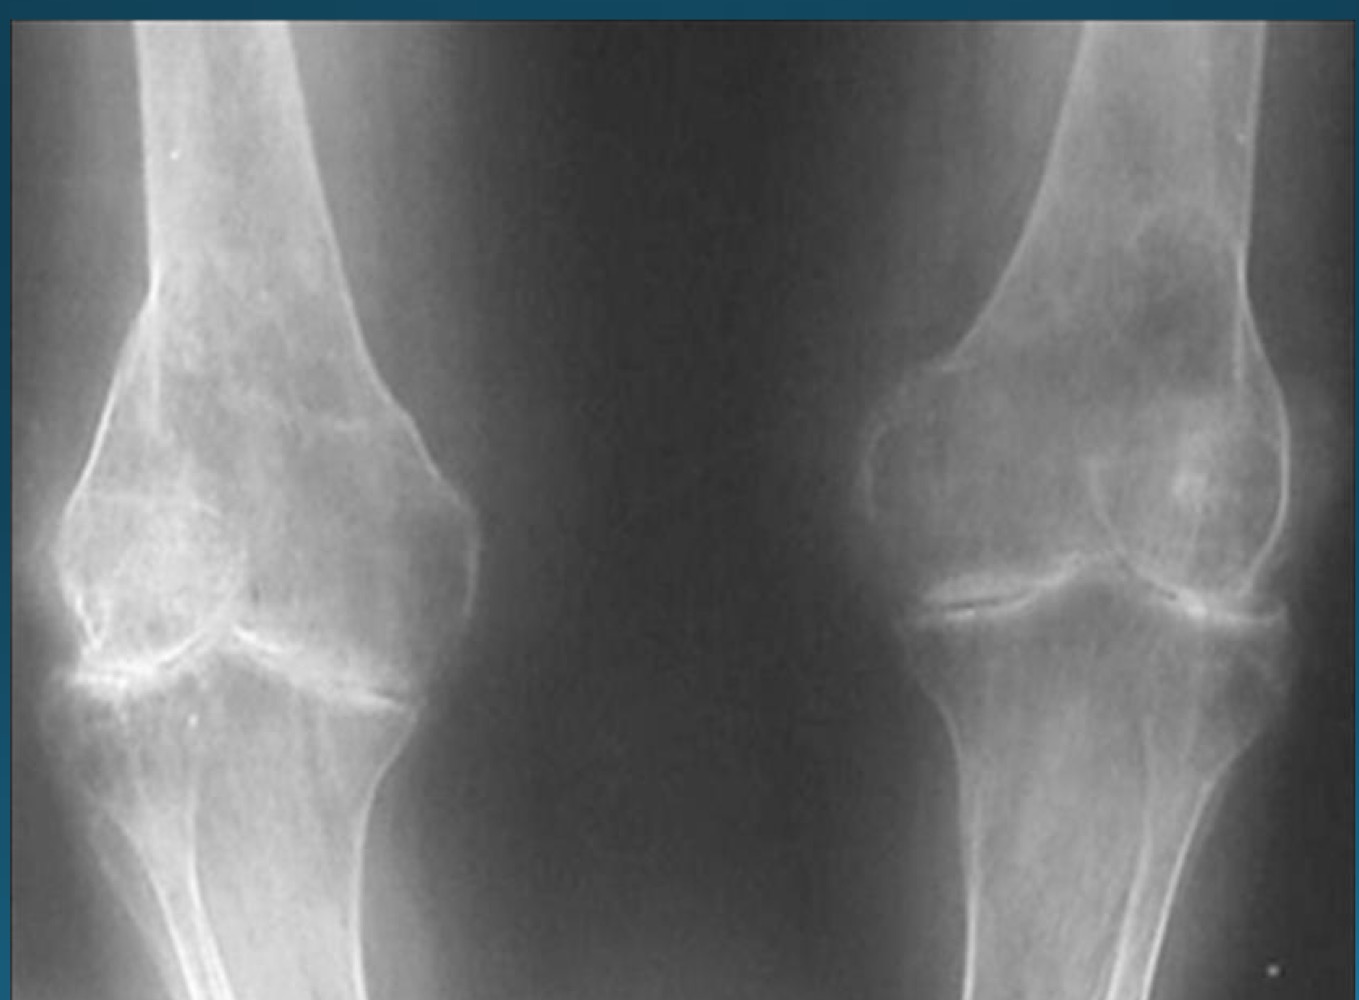

what finding is in this image

hypertrophic neuropathic arthropathy

what is the finding in this image? AKA

neuropathic arthropathy AKA charcot’s joint

atrophic neuropathic arthropathy

what appearance does atrophic neuropathic arthropathy typically take on ?

licked candy stick

what would this charcot joint be caused by

syphilis

syringomyelia

diabetes